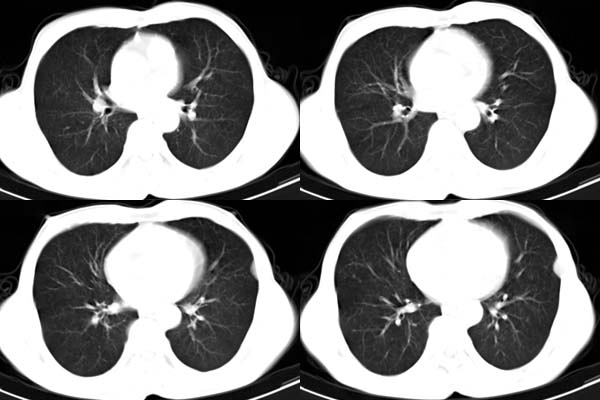

患者,男,65岁,咳嗽,胸痛

ct所见;左下肺可见片状阴影,密度不均,边缘尚清晰,胸膜方向见有条索相连,纵隔窗未见具体结节。左侧胸膜下见多个软组织结节且以宽基底与胸膜相连,右侧胸锁关节层面亦见软组织结节广基与胸膜相连。纵隔未见肿大淋巴结,气管,支气管开口正常。

左肺下叶基底段见结节样稍高密度影,内密度不均匀,边缘不清,可见索条影与邻近胸膜粘连,左侧胸膜上见多个结节影,以宽基底与胸膜粘连.纵隔不宽,内未见明确肿大的淋巴结.

ct所见:左肺上、下叶近胸膜肺外带可见多个大小不等的结节灶,边界清楚,边缘比较光整。近胸膜病灶似与胸膜以宽基底紧连。提供的病史比较简单,我考虑:1、胸膜原发肿瘤可能性大(就形态来看恶性可能性不大);那么大胆的设想一下,左下叶结节是否与它有必然的联系呢?也可以是结核或周围型肺癌。2、还可以考虑为胸膜和肺内的都是转移灶,病人65岁,是不是其他部位的恶性肿瘤转移过来的呢?因为病灶比较表浅,但一侧发病较少见。3、周围型肺癌并胸膜转移的可能性比较小,一是肺内病灶较小,单发,胸膜结节相对较多,位置较远,临近胸膜无受侵。